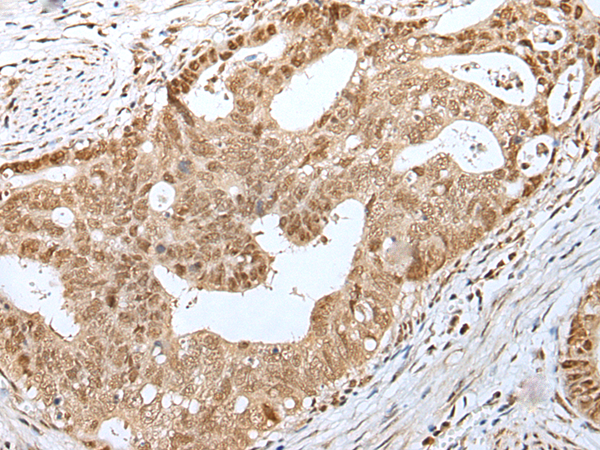

ELISA, IHC |

IHC positive control: |

Human gastric cancer and human tonsil |

IHC Recommend dilution: |

25-100 |